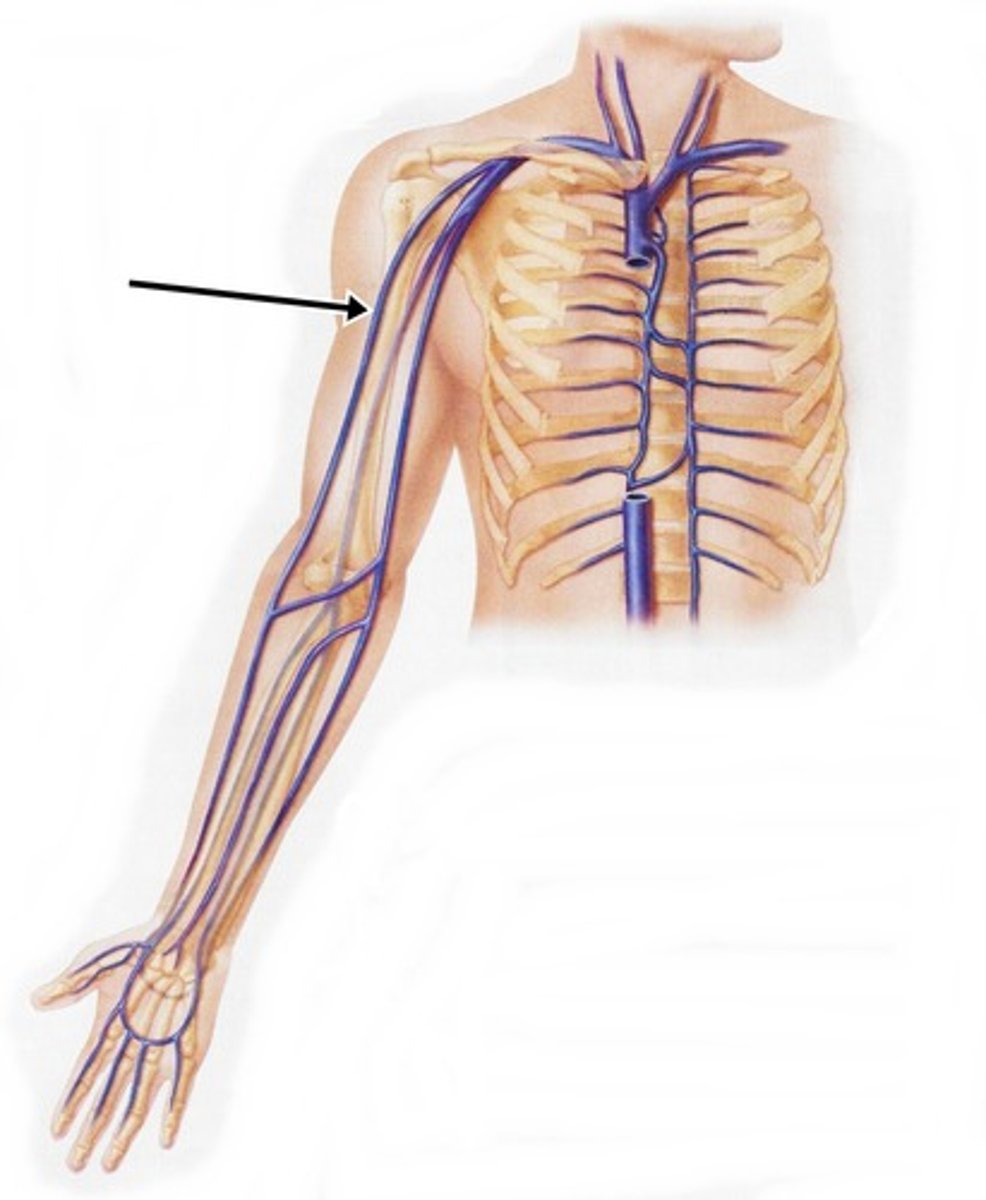

subclavian vein

superior vena cava

axillary vein

brachial vein

cephalic vein

radial vein

ulnar vein